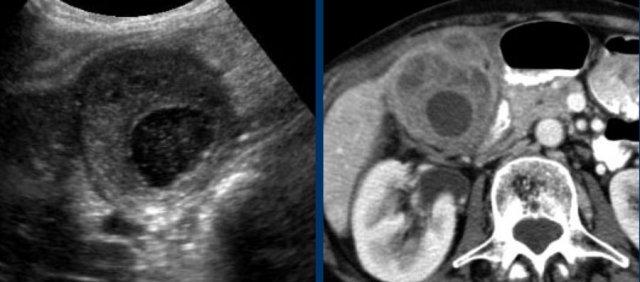

Bệnh nhân béo phì với đau thượng vị cấp tính.

Siêu âm cho thấy sỏi túi mật và dày thành, gợi ý viêm túi mật cấp.

CT thực hiện tiếp theo đã phát hiện bản chất thực sự của các triệu chứng: viêm tụy cấp do sỏi mật với dày thành túi mật thứ phát.